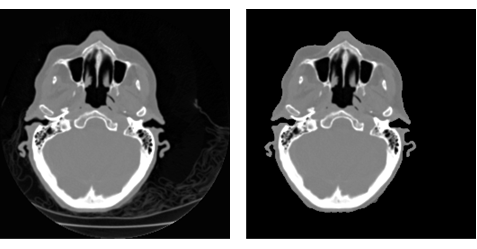

분할 및 분할 선택 방법을 사용하여 이미지에서 배경의 특징을 제거합니다. 이것은 특히 볼륨 재구성에 편리합니다.

res = ImageMultiply[i, SelectComponents[FillingTransform@Binarize[i], "Area", -1]]; GraphicsRow[{i, res}]